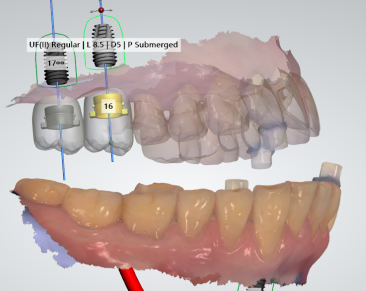

『진단 화면』

이렇게 3D 로 구현이 되면서 컬러로 구현이 되어서

조금 더 직관적으로 볼 수 있게 하는것이 바로

네비게이션 임플란트 진단 방식입니다.

Implant fixture 들이 심겨지는 치조골의

여러가지 정보들을 한 눈에 습득을 할 수 있기

때문에 술자의 입장에서는 조금 더 객관적인

진단이 가능합니다.

그래서 이렇게, 미리 사진 예상 식립위치를

결정 한 다음에는

곧바로 수술에 들어가게 됩니다.